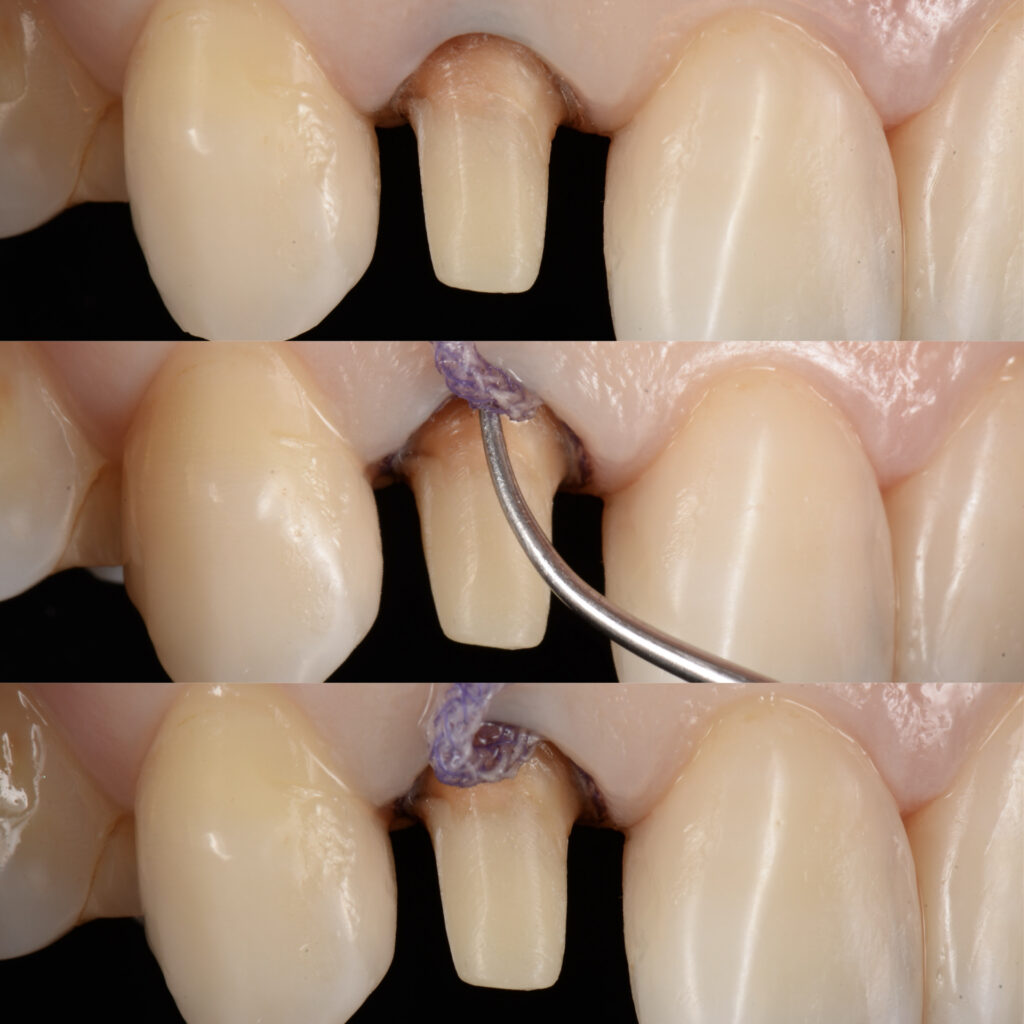

当院では

以下のようにして、精度の高い詰め物や被せ物を作製しております。

上記のように丁寧に形を整え、歯肉と歯の隙間(歯周ポケット)に糸を本巻きます。

そして、型取りの材料を入れる直前に、その糸を取り去ります。糸の太さ分開いた歯肉と歯の隙間に型取りの材料を流し込んでいくと、型取った際に上記のように歯肉と歯の境目が明瞭に浮き出てきます。

そうすることで、歯と歯肉の境目が模型上に反映され、適合の良い詰め物や被せ物を作製することができます。

この際使用している型取りの材料は、変形量の少ないシリコン性のものを使用しておりますので、材料によるエラーは極力生じないようにしております。